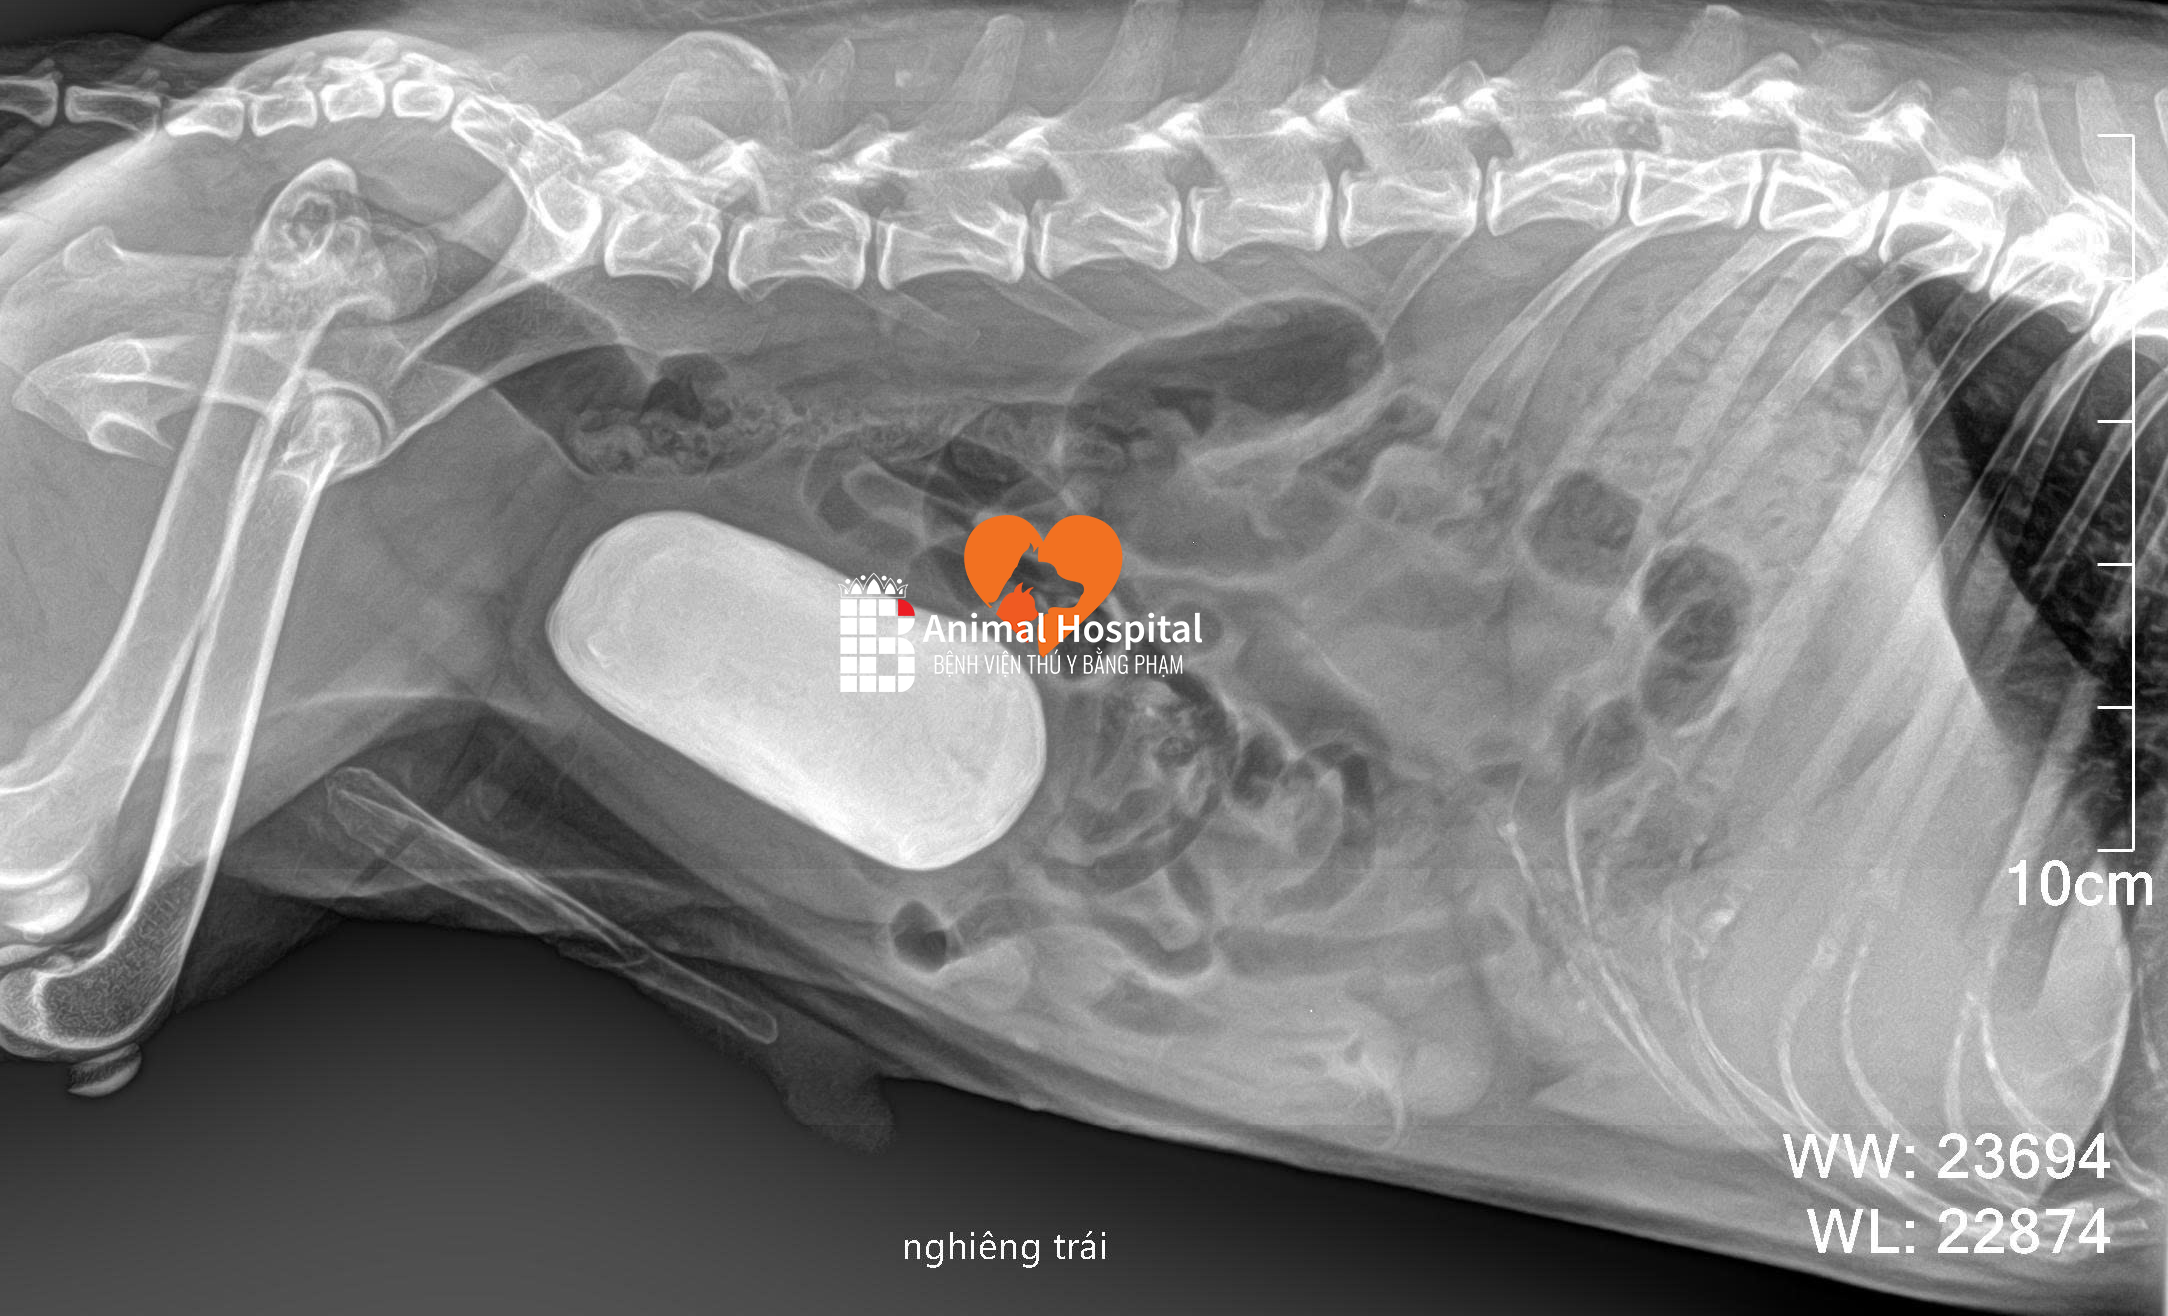

Khám – chụp X-quang, đánh giá góc xương chày, mức độ thoái hóa khớp gối

Phẫu thuật TPLO: cắt một đoạn xương chày theo hình bán nguyệt, xoay đoạn này để tạo góc mới phù hợp, sau đó cố định bằng bản kim loại và vít